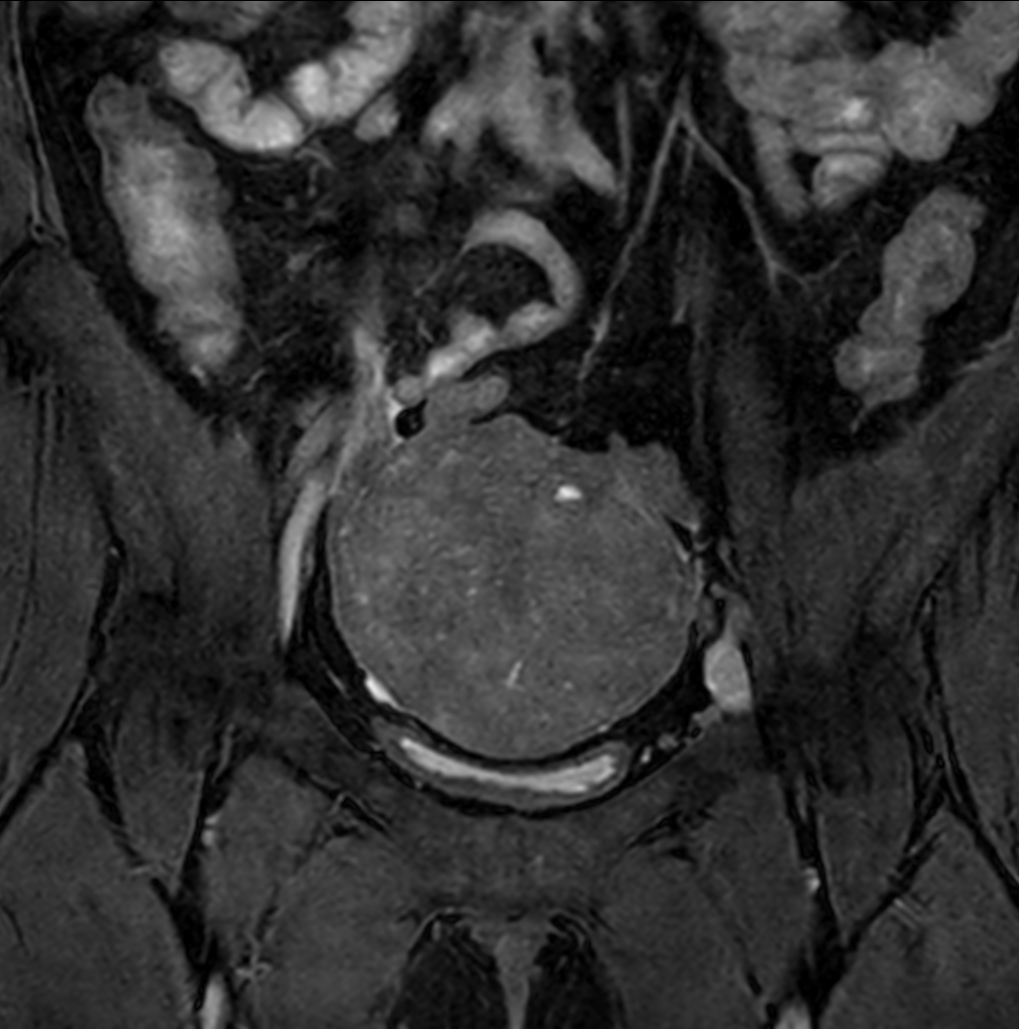

Axial T2w TSE